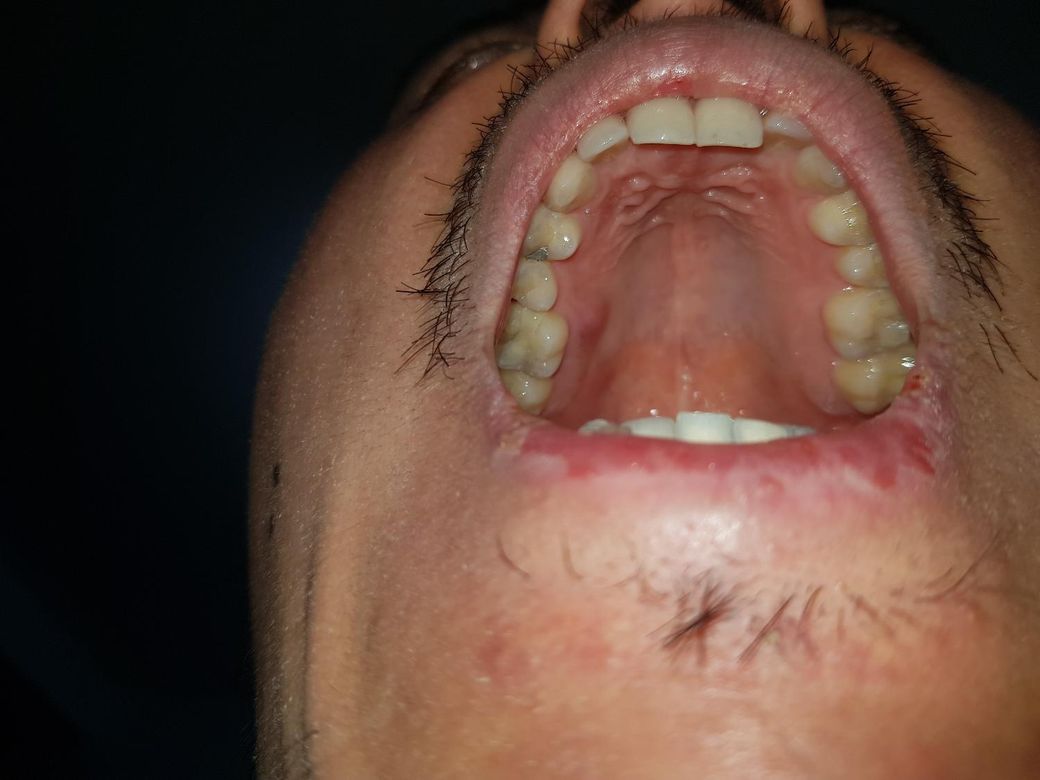

다음날 이물감 거의없이 있다 하루뒤 오늘은 다시 입천장이 원래 딱딱하기만 해야하는데 살짝 물컹거리는 이물감이 또 느껴집니다 내일되면 또 작게 올라올거같습니다

집이 병원이랑 거리가멀어서 쉽게 갈수가없어요

가야한다면 어떻게설명하는게 최선일까요?

현재 사진상 문제가 되어 보이지는 않습니다. 물집을 억제로 터뜨리며 균감염 우려가 있기에 다시 올라와도 터뜨리지 말고 헥사메딘 가글액으로 소독을 하여 관리하고, 점막 재생을 돕는 비타민비군제품을 약국에서 구매하여 복용을 권합니다.

만약 통증이 심하고 반복시에는 치과 진료나 이비인후과진료를 받아보길 권합니다.

잇몸염증이 잇엇던거 같습니다. 치과에 가셔서 입천장이 부엇다고 말씀하시면 엑스레이를 찍어보시고 치료를 받으시는게 좋을것같습니다.